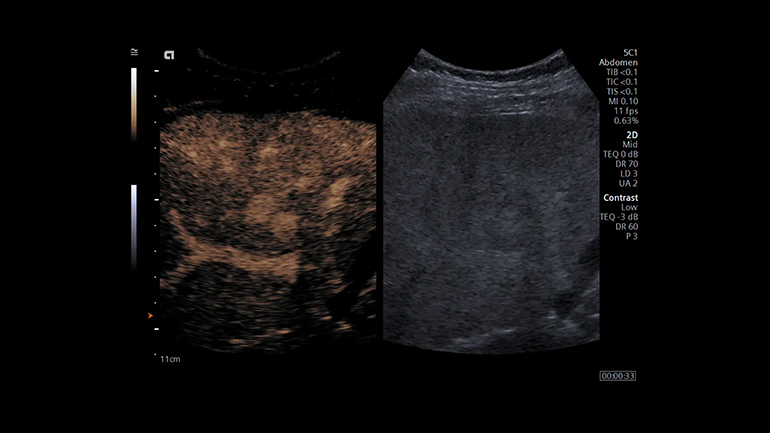

Технология визуализации эластичности ткани с использованием мануальной компрессии для линейных датчиков. Метод мануальной деформационной эластографии Virtual Touch обеспечивает простое и качественное измерение жесткости пораженного участка относительно окружающих неповрежденных тканей. УЗИ с контрастным усилением (CEUS) с помощью визуализации с контрастным веществом. Технология импульсных последовательностей контрастного усиления эхо-сигнала от микропузырьков контрастного препарата (CPS) и технология коротких импульсов с большим механическим индексом позволяют более уверенно диагностировать очаги поражения печени.

УЗИ с контрастным усилением (CEUS) с помощью визуализации с контрастным веществом. Технология импульсных последовательностей контрастного усиления эхо-сигнала от микропузырьков контрастного препарата (CPS) и технология коротких импульсов с большим механическим индексом позволяют более уверенно диагностировать очаги поражения печени. Технология визуализации векторного анализа кардиомиокинетики syngo Velocity Vector Imaging (VVI). Данная недоплеровская технология позволяет визуализировать вектор скорости и амплитуду смещения любого локуса миокарда. Таким образом, позволяет неинвазивно оценить локальную и глобальную сократимость миокарда независимо от угла сканирования.